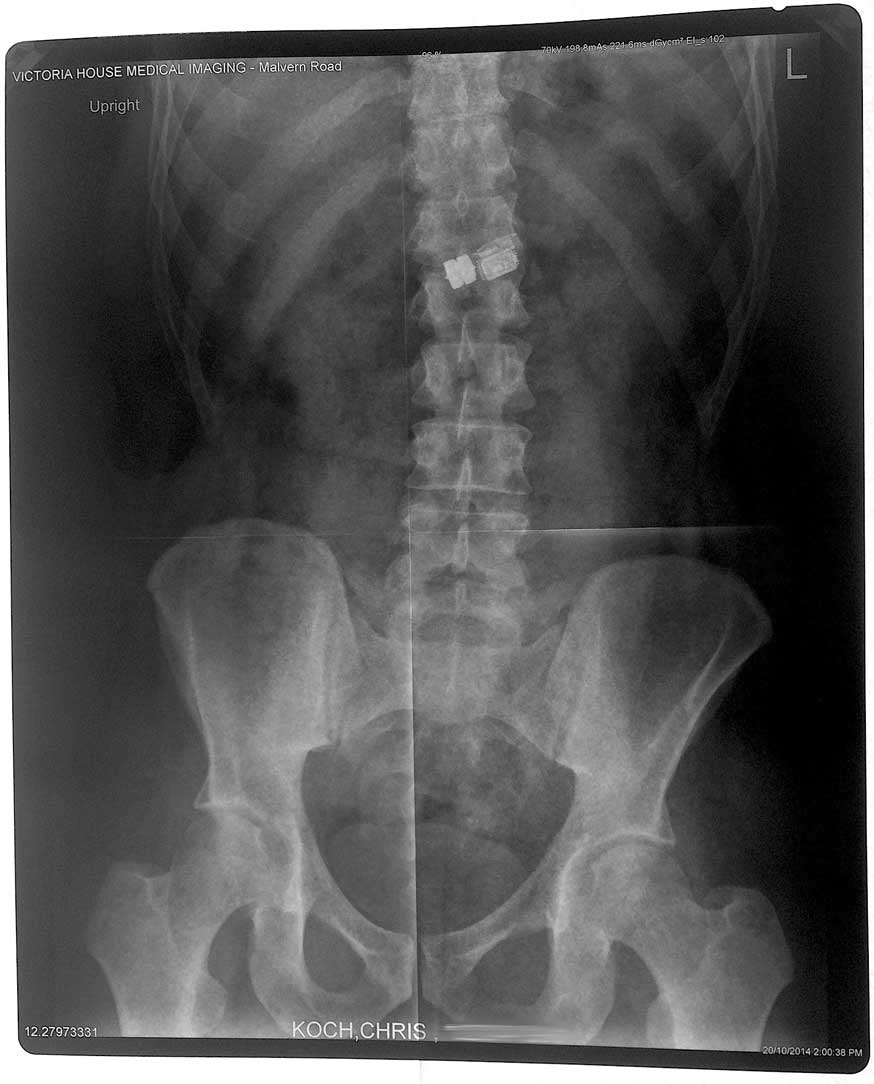

- The x-ray showing the device inside chris

As part of the ‘Pop! The Boss’ competition, which started on Monday 20 October 2014 in Melbourne, Australia, Koch swallowed a large pill live on streaming video containing a computer chip. Every time someone enters the competition, their details will be sent to the computer chip inside of him via Bluetooth. Because of the battery life required to keep the computer running for 24 hours, the pill itself is quite large — about 3.5cm by 2cm — considerably larger than your average vitamin tablet.